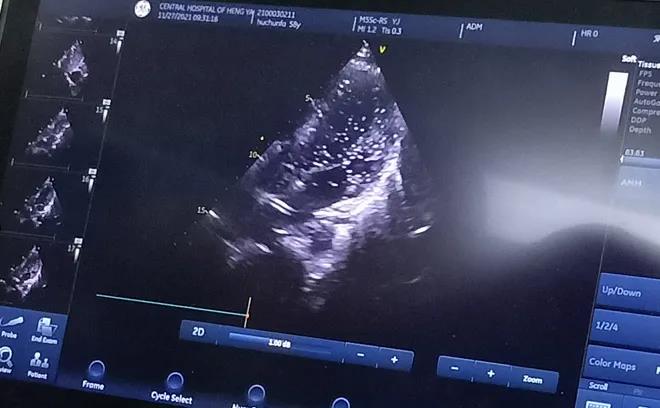

經(jīng)充分的術(shù)前準(zhǔn)備后, 11月27日上午,胡先生接受局部麻醉下經(jīng)皮介入PFO封堵術(shù),手術(shù)全程病人清醒,醫(yī)生一邊與胡先生交流,一邊進(jìn)行手術(shù),術(shù)后無(wú)傷口創(chuàng)面?;颊弋?dāng)天即下床活動(dòng),復(fù)查心臟彩超提示封堵器位置良好。

胸超聲心動(dòng)圖引導(dǎo)下經(jīng)股靜脈房間隔缺損封堵術(shù)是在胸超聲心動(dòng)圖實(shí)時(shí)監(jiān)測(cè)下的封堵術(shù),與傳統(tǒng)開(kāi)胸行房間隔缺損修補(bǔ)術(shù)相比,只需要通過(guò)大腿股靜脈進(jìn)行穿刺便可完成,出血少、不縫針,真正做到了“微創(chuàng)”,創(chuàng)傷小且不影響美觀;與內(nèi)科介入下手術(shù)相比,又避免了X線對(duì)患者的放射損傷。在胸超聲實(shí)時(shí)引導(dǎo)下操作,定位準(zhǔn)確,隨時(shí)可調(diào)整封堵傘位置,適合于繼發(fā)孔房間隔缺損、室間隔缺損、動(dòng)脈導(dǎo)管未閉等各種常見(jiàn)先天性心臟病的治療,對(duì)先心病心臟病患者的治療又提供了一項(xiàng)新的微創(chuàng)治療方法。該技術(shù)因創(chuàng)傷小、恢復(fù)快,術(shù)后3至5天即可出院。